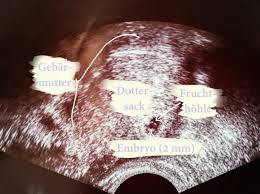

5 ssw ultraschall nur fruchthöhle. In der Frühschwangerschaft können Frauenärzte nicht immer bei der ersten Ultraschalluntersuchung das Baby oder den Herzschlag im Ultraschall erkennen. SSW eine Fruchthöhle und frühestens ab der 6. Guten Abend ich hatte heute meinen 1.

Ultraschallbild Fruchthöhle 5 SSW 3 Beitrag 6 Erstmal herzlichen Glückwunsch zur Schwangerschaft. Allzu viel wirst du auf dem Monitor nicht erkennen können aber bei einer Ultraschalluntersuchung kann ab der 4. Ssw nachdem sich in der 1.

Man konnte nur eine leere fruchthöhle erkennen. Frauenarzt Termin laut Ultraschall bin ich ssw 55 wobei allerdings nur eine leere fruchthöhle zu sehen war von 095cm. Ich habe eine kurze Frage.